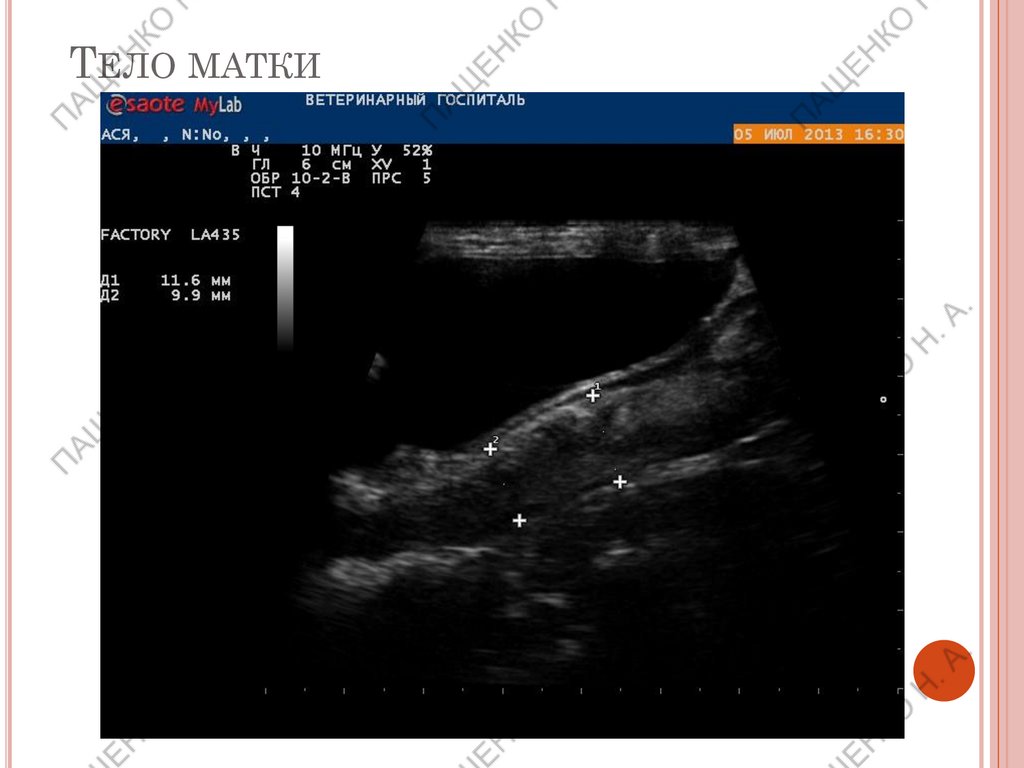

ТЕЛО МАТКИ

10.